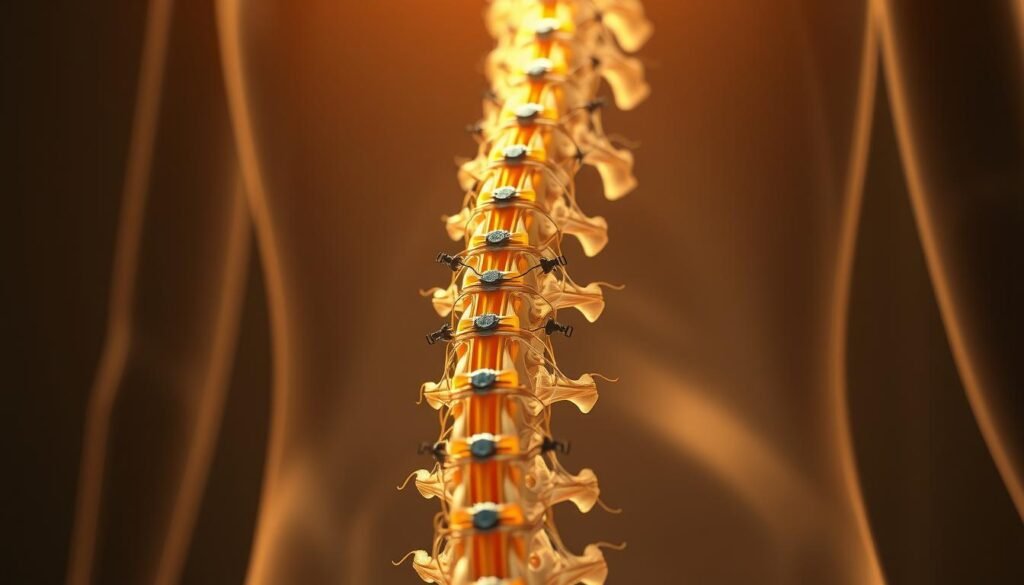

A small array of leads sits beside the spinal cord to alter overactive nerve signaling before it reaches the brain. Spinal cord stimulation places thin leads near the cord to modulate pathways and reduce the intensity of messages that travel to the brain.

This next-generation system uses a small implanted generator and fine leads to provide round-the-clock high-frequency therapy near the spinal cord.

HFX is a compact device placed under the skin with thin, flexible leads beside the cord. It delivers gentle 10‑kHz stimulation that many patients find comfortable and paresthesia-free.

Outpatient implant: thin leads near the spinal cord, small device under the skin

The implant procedure is minimally invasive and done with fluoroscopic guidance to place thin leads near the cord. A small generator sits under the skin and most patients go home the same day.